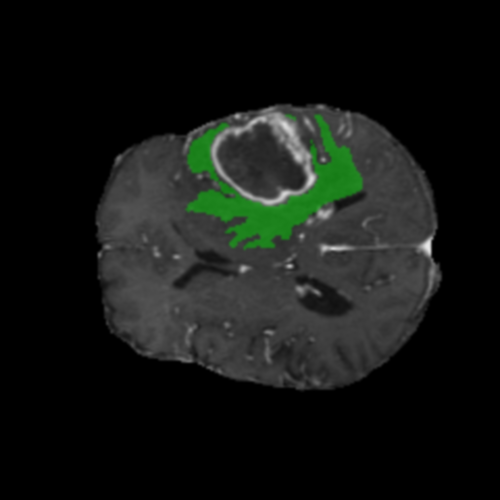

Ejemplos de Modalidades MRI

Visualización de las 4 modalidades de resonancia magnética y las segmentaciones de zonas tumorales utilizadas para entrenar el modelo

Núcleo HGG

Núcleo

Edema HGG

Edema

Realce HGG

Realce

Tumor Completo HGG

Tumor Completo

Núcleo Edema Realce